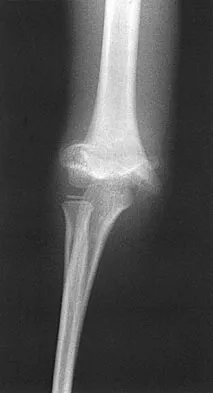

Figure 38 shows the radiograph of a 16-year-old wrestler who injured his elbow when he was thrown to the mat by his opponent. To minimize additional trauma to the medial soft tissues, the elbow should be reduced in